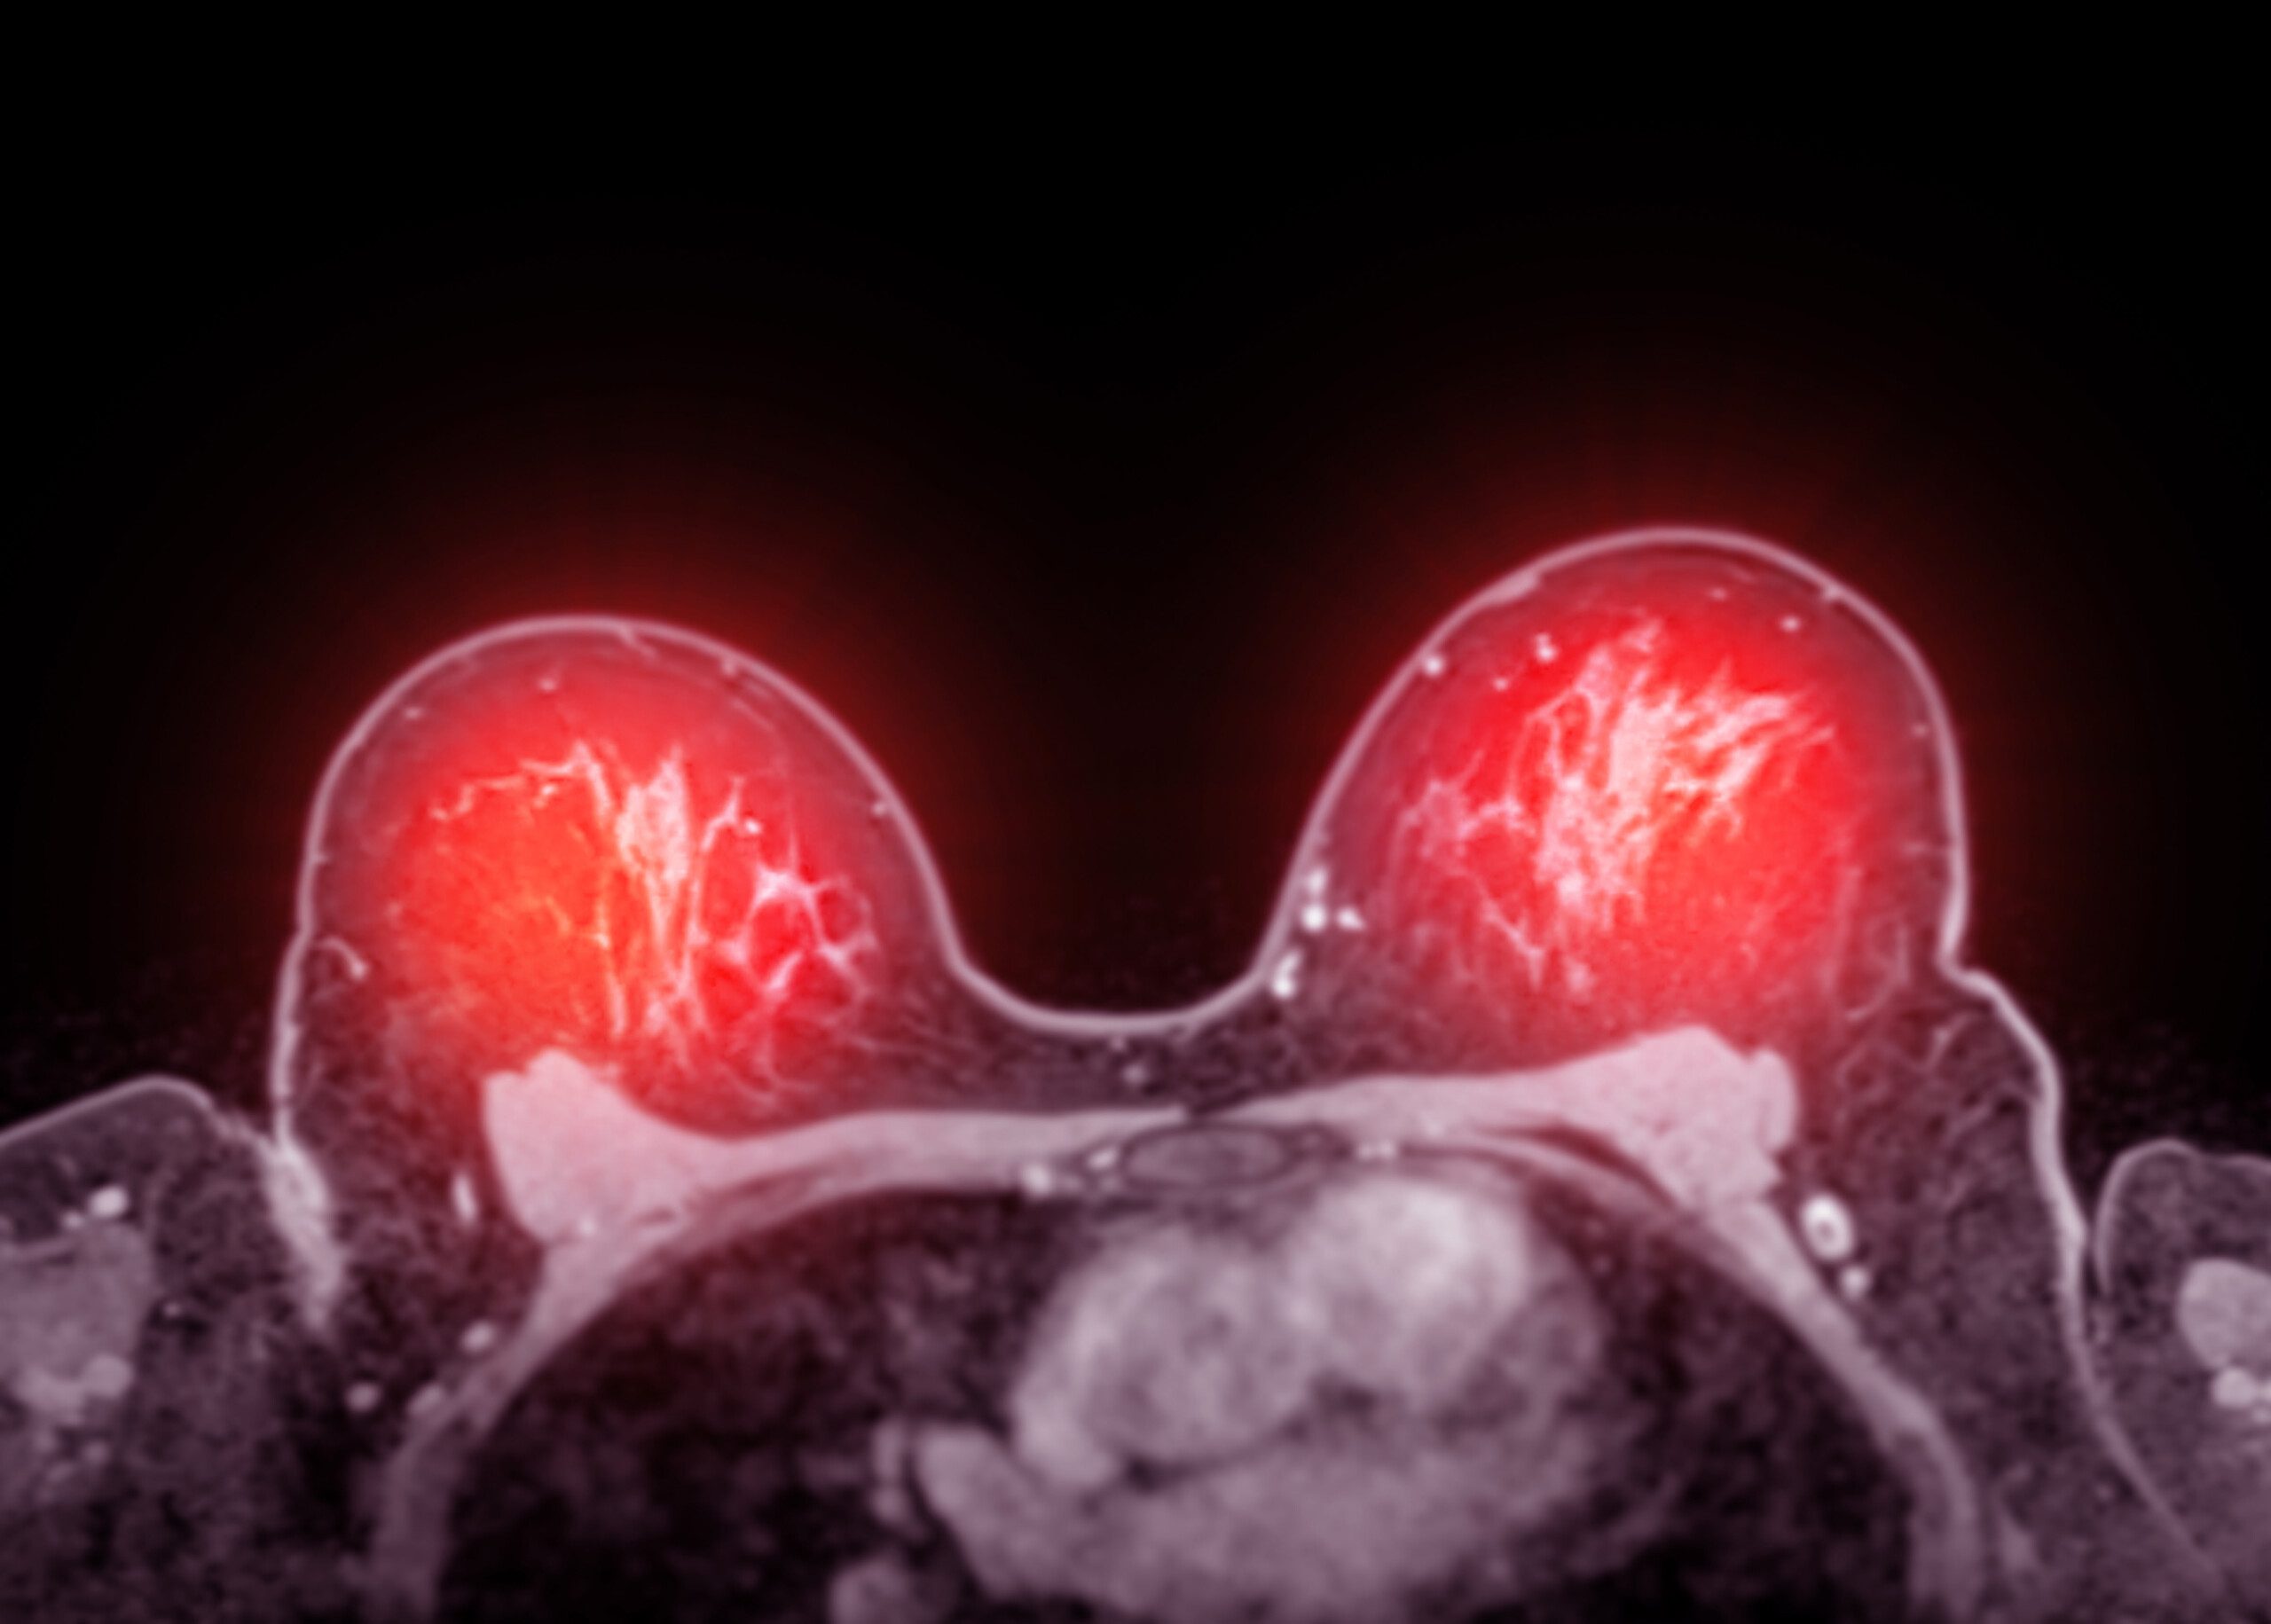

Beim frühen Hormonrezeptor-positiven Brustkrebs kann in vielen Fällen auf eine zusätzliche Chemotherapie verzichtet werden. Die Online-Entscheidungshilfe "Früher Brustkrebs: Chemotherapie - ja oder nein" will Patientinnen und Patienten über die Behandlungs-möglichkeiten aufklären und sie so bei der Entscheidungsfindung unterstützen.

In unserem Special informieren wir Sie darüber, was die BRCA-Gene überhaupt sind und welche Auswirkungen sie auf Brustkrebs haben.

Lesen Sie jetzt in unserem Spezial alles rund um das Thema metastasierter Brustkrebs.